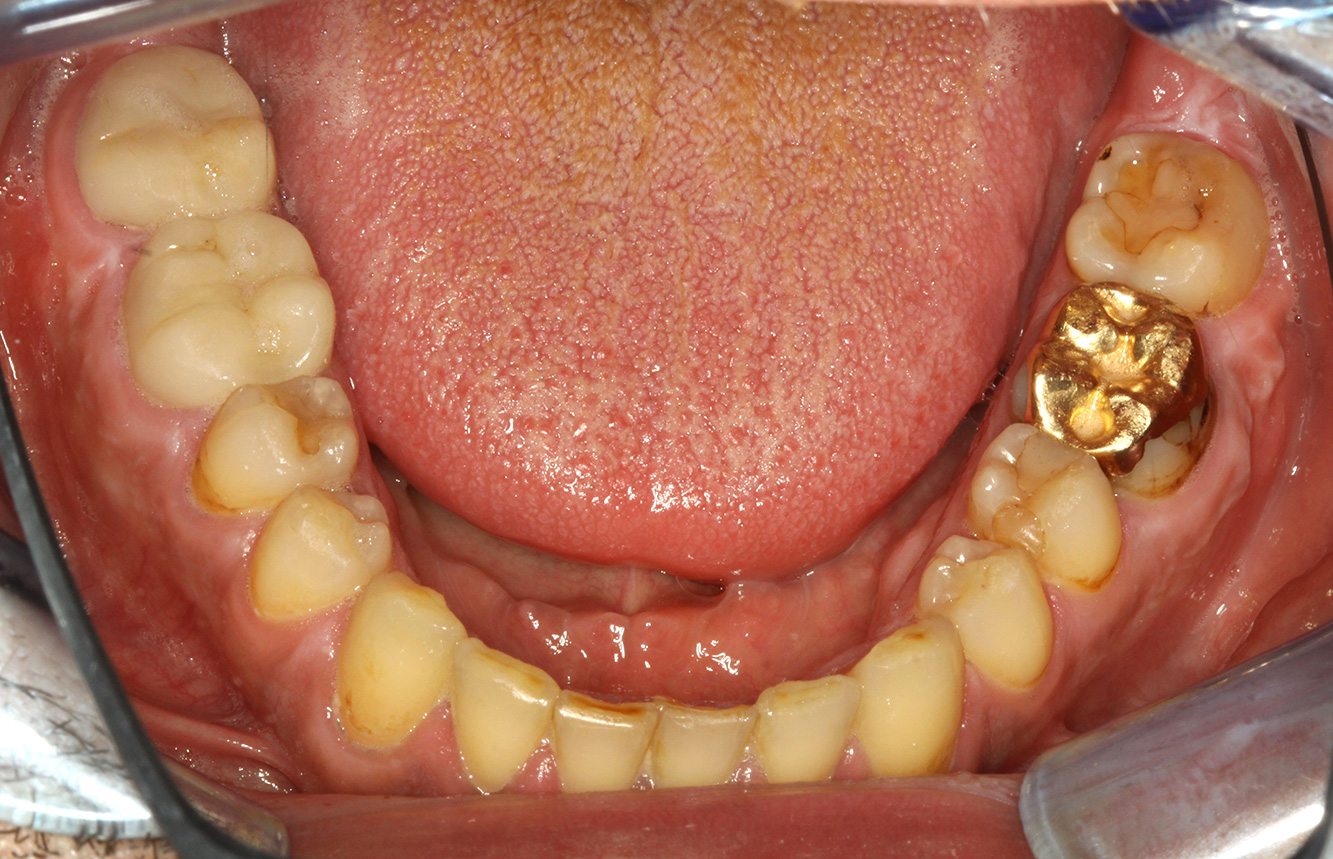

Bedingt durch die aktiven Kariesläsionen und dem damit einhergehenden Progressionsrisiko ergibt sich ein verkürztes Recall-Intervall von drei bis vier Monaten.

* mit freundlicher Genehmigung von Dr. G. Schmalz und Prof. Dr. D. Ziebolz MSc.